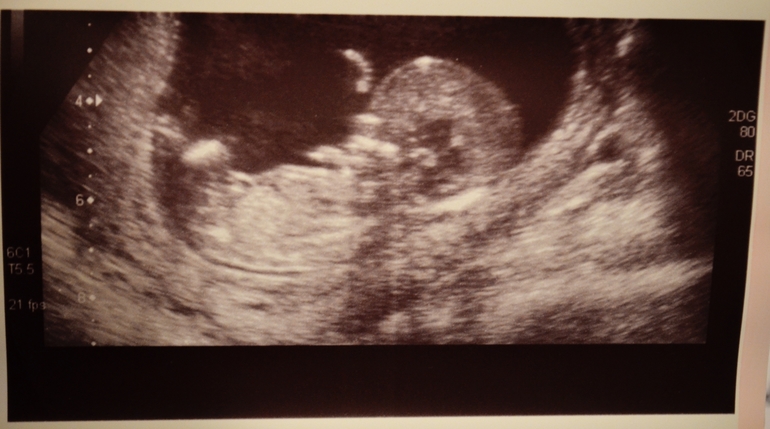

Делают Ли Фото На 1 Скрининге⚡ 👉🏻👉🏻👉🏻 ВСЯ ИНФОРМАЦИЯ ДОСТУПНА ЗДЕСЬ, КЛИКАЙ 👈🏻👈🏻👈🏻Делают Ли Фото На 1 Скрининге